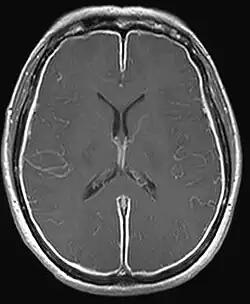

Strongyloides infection occurs in several forms. As the infection continues and the larvae matures, there may be respiratory symptoms (Löffler's syndrome). The infection may then become chronic with mainly digestive symptoms. On reinfection from the skin to the lungs and finally to the small intestine, there may be respiratory, skin and digestive symptoms. Finally, the hyperinfection syndrome causes symptoms in many organ systems, including the central nervous system.[11][12][4]

Disseminated strongyloidiasis occurs when patients with chronic strongyloidiasis become immunosuppressed. There is a distinction to be made between dissemination and hyperinfection. It is mainly a semantic distinction. There can be mild dissemination where the worm burden is relatively lower yet causes insidious symptoms, or extreme dissemination that the term hyperinfection is used to describe. Thus hyperinfection of varying levels of severe dissemination may present with abdominal pain, distension, shock, pulmonary and neurologic complications, sepsis, haemorrhage, malabsorption, and depending on the combination, degree, number, and severity of symptoms, is potentially fatal. The worms enter the bloodstream from the bowel wall, simultaneously allowing entry of bowel bacteria such as Escherichia coli. This may cause symptoms such as sepsis,[14] and the bacteria may spread to other organs where they may cause localized infection such as meningitis.[15] Dissemination can occur many decades after the initial infection[16] and has been associated with high dose corticosteroids, organ transplant, any other instances and causes of immunosuppression.[17][18]